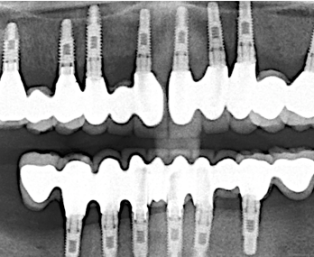

Zahnimplantate

Zahnimplantate bieten seit mehr als 50 Jahren die Möglichkeit, verloren gegangene Zähne langfristig und vollwertig zu ersetzen. Die Implantologie gehört mittlerweile zu den Standardtherapien in der Zahnheilkunde und basiert auf einem soliden wissenschaftlichen Fundament.